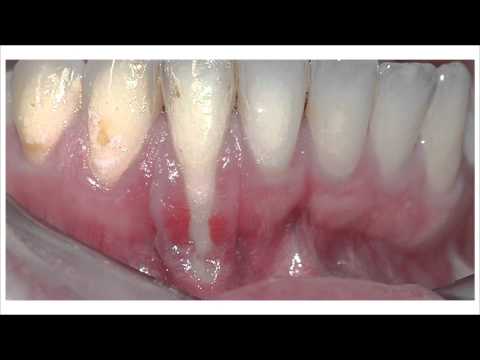

Hablando de Salud Oral 05-28-15 (03) - Contestando los Textos sobre las Encías

Hablando de Salud Oral 05-18-15 (02) - La oficina del Dr. Fernando Sosa

Hay Que Decirlo 05-07-15 (05) - Dr. Fernando Sosa explica sobre los distintos dentistas